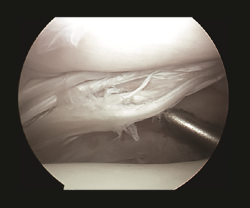

El pinzamiento posterolateral puede ser causado por un desgarro del ligamento tibioperoneo transverso y/o el ligamento intermaleolar posterior (túnel osteofibroso tibial). Rosenberg et al. identificaron que se hallaba presente en un 56% de las piezas anatómicas de su trabajo. Estos autores lo describen con unas dimensiones de entre 1 y 8 mm de ancho y entre 5 y 8 mm desde anterior a posterior. Encontraron que era una variante normal de los ligamentos posteriores del tobillo y explicaron así cómo se pueden producir los síntomas de pinzamiento posterior(11). Personalmente, hemos realizado y descrito el desbridamiento de roturas del ligamento tibioastragalino transverso en 25 pacientes con buen resultado y sin complicaciones posteriores(12)(Figura 7).

Figura 7. Desgarro longitudinal del ligamento transverso en un tobillo derecho de un jugador de baloncesto antes de practicar su desbridamiento.